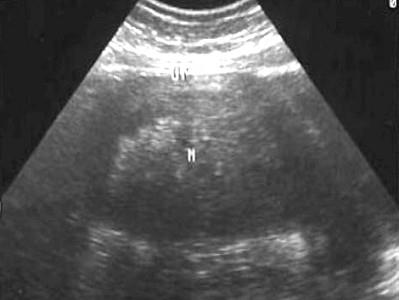

问题 女性,46岁,月经量不多,无痛经史,超声检查见图,最可能的诊断是 ( )

选项 A、子宫腺肌症 B、正常声像图 C、子宫内膜癌 D、宫颈肥厚 E、子宫肌瘤

答案 E